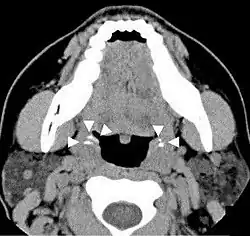

![]() | |

| A tonsillolith lodged in the tonsillar crypt | |

Imaging diagnostic techniques can identify a radiopaque mass that may be mistaken for foreign bodies, displaced teeth or calcified blood vessels. CT scan may reveal nonspecific calcified images in the tonsillar zone. The differential diagnosis must be established with acute and chronic tonsillitis, tonsillar hypertrophy, peritonsillar abscesses, foreign bodies, phlebolites, ectopic bone or cartilage, lymph nodes, granulomatous lesions or calcification of the stylohyoid ligament in the context of Eagle syndrome (elongated styloid process).[18]